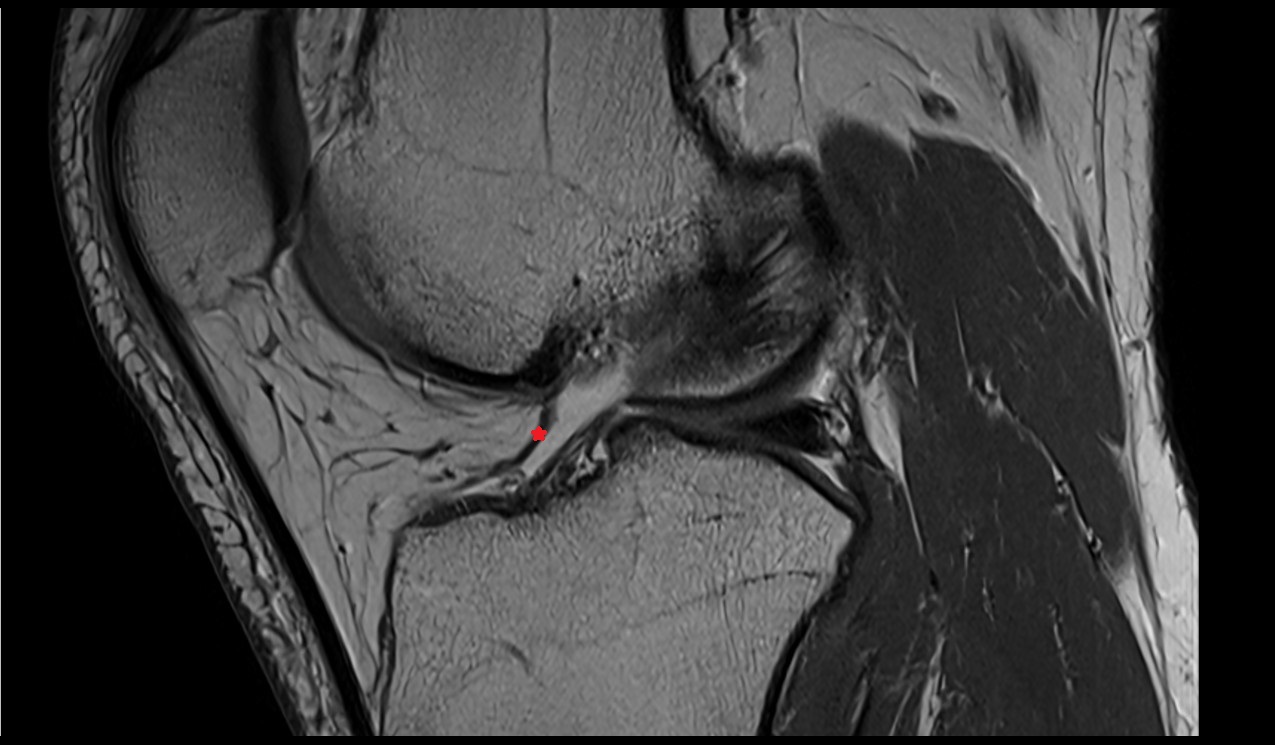

- Anterior cruciate ligament

- Posterior cruciate ligament

- Medial meniscus

- Lateral meniscus

- Knee Joint